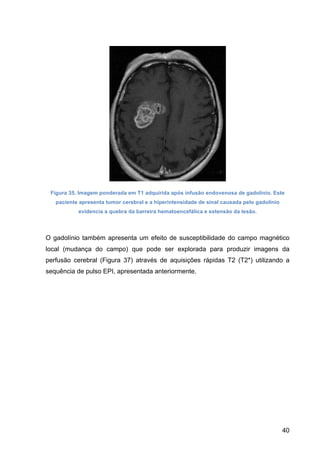

Figura 35. Imagem ponderada em T1 adquirida após infusão endovenosa de gadolínio. Este

paciente apresenta tumor cerebral e a hiperintensidade de sinal causada pelo gadolínio

evidencia a quebra da barreira hematoencefálica e extensão da lesão.

O gadolínio também apresenta um efeito de susceptibilidade do campo magnético

local (mudança do campo) que pode ser explorada para produzir imagens da

perfusão cerebral (Figura 37) através de aquisições rápidas T2 (T2*) utilizando a

sequência de pulso EPI, apresentada anteriormente.